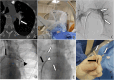

Endovascular retrieval of a contraceptive implant in the pulmonary artery. A A CT scan in the axial section showing a contraceptive device partially located in a left lower lobe segmental artery and the left pulmonary artery (white arrow). B The patient was placed in a dorsal decubitus position in a biplane interventional room, using both left and right anterior obliquities. C After a right femoral approach, an angiogram using a 5F pigtail showed the contraceptive device (white arrows), with no visible thrombosis. D A 8F introducer was placed into the left pulmonary artery (black arrow), allowing insertion of a 6F sheath and a loop snare (black arrowhead). E After pulling the contraceptive device (white arrows) with the loop snare (white arrowhead), it was then locked in front of the sheath and the introducer (black arrow). F After removing the entire introducer, the contraceptive device (white arrows) was trapped by the loop snare (black arrow)